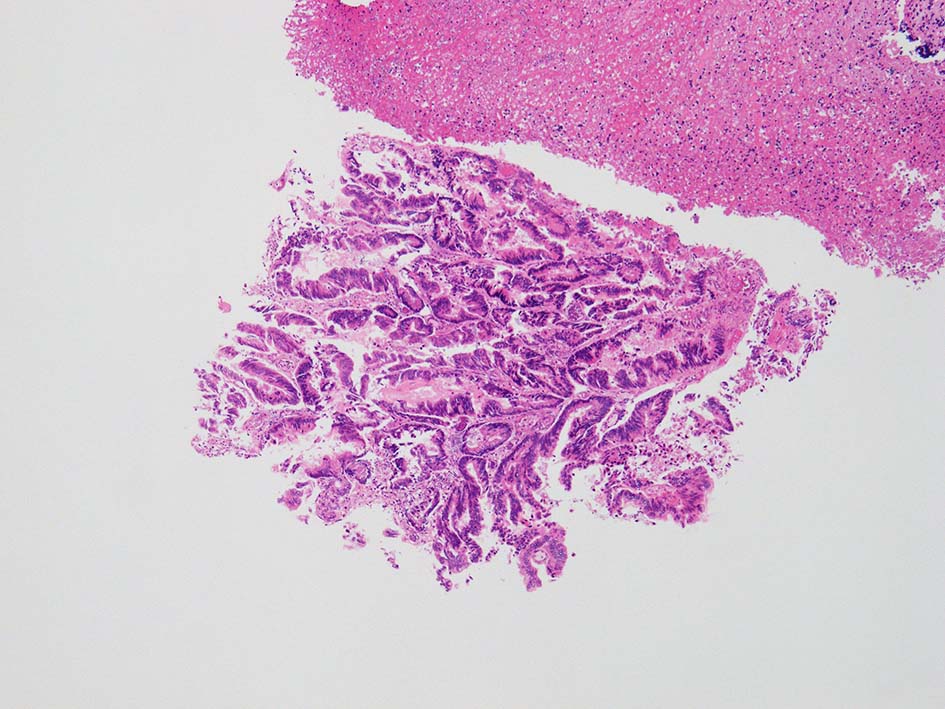

膀胱鏡検査で頸部6時方向に乳頭状腫瘤があり, 膀胱がん疑いで生検をおこなう.

腸管型の腺癌。大腸の高分化腺癌と組織学的に区別は難しい.